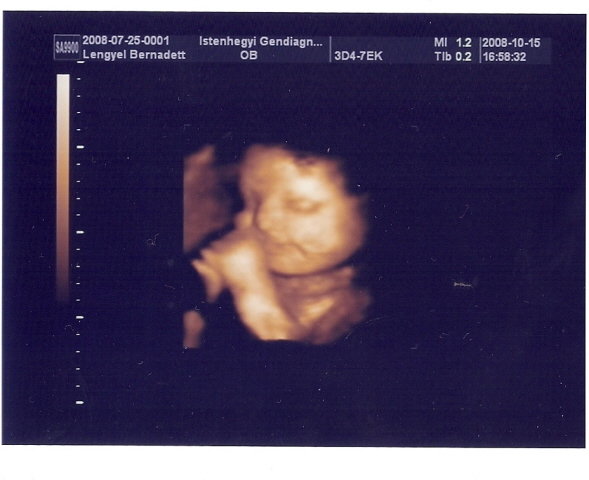

Jó reggelt Csajok!

Tegnap jártunk UH-n, Zsófival minden ok, csak kicsit nagyobb az átlagnál. Végig vigyorogta az UH-t, lehet azért, mert betoltam egy Sport csokit a vizsgálat előtt. :-D Amúgy meg rám hasonlít!!!

32+1-es adatok:

BPD: 87,9 mm

HC: 313,3 mm

AC: 291,6 mm

FL: 64,7 mm

TAD: 84,7 mm

Becsült súly: 2240 g :-D

Az adatok alapján 33+6-nak felel meg. :-D

Az ékes bizonyíték, hogy kislány!!!!